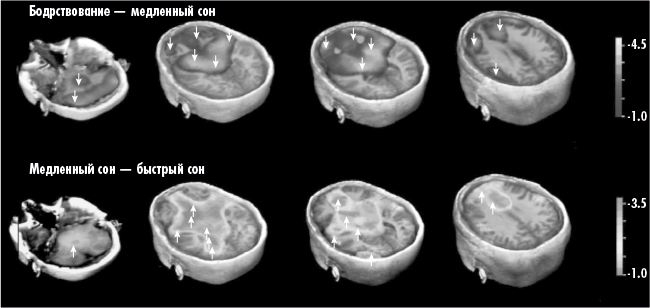

Рис. 3. В горизонтальных рядах (слева направо) представлены срезы мозга от нижней части к верхней. В верхнем ряду показаны различия между бодрствующим и спящим мозгом: выделенная темным область демонстрирует понижение активности коры при засыпании; в нижнем ряду – различие между быстрым и медленным сном: выделенная светлым область соответствует повышению подкорковой активности в начале фазы быстрого сна. Наибольшая активность наблюдается там, где расположена ПОИСКОВАЯ система

Дофаминергическая ПОИСКОВАЯ активность (в отличие от всякой другой моноаминовой активности) продолжается при засыпании и достигает максимума в фазе быстрого сна. Возможно, не случайно это совпадает с периодами быстрого движения глазных яблок. Движения глаз у человека, подобно обнюхиванию и подергиванию вибриссами у грызунов, – неплохой косвенный показатель ПОИСКОВОЙ активности (Panksepp, 1998).

58